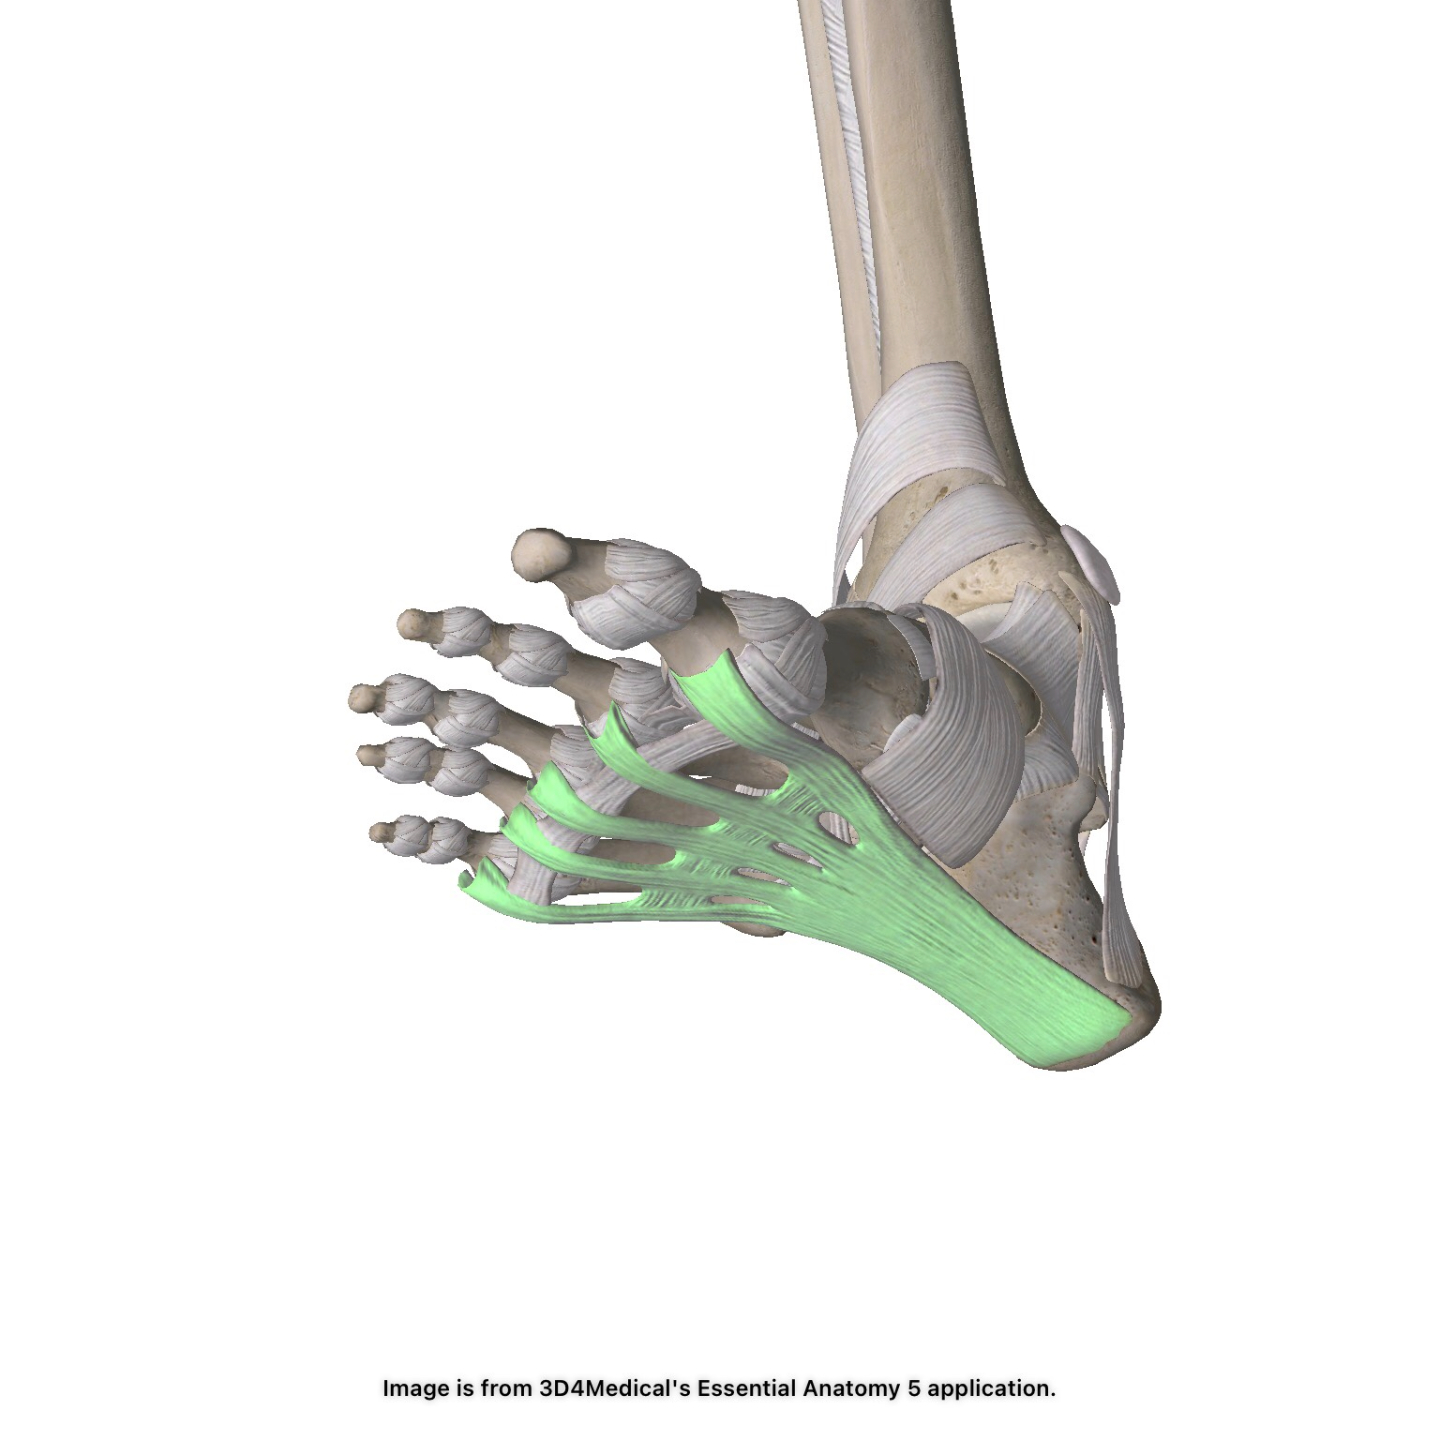

Bruises & Sprains & Strains! Oh My!

Our take on the most modern approach to treating minor sports injuries.